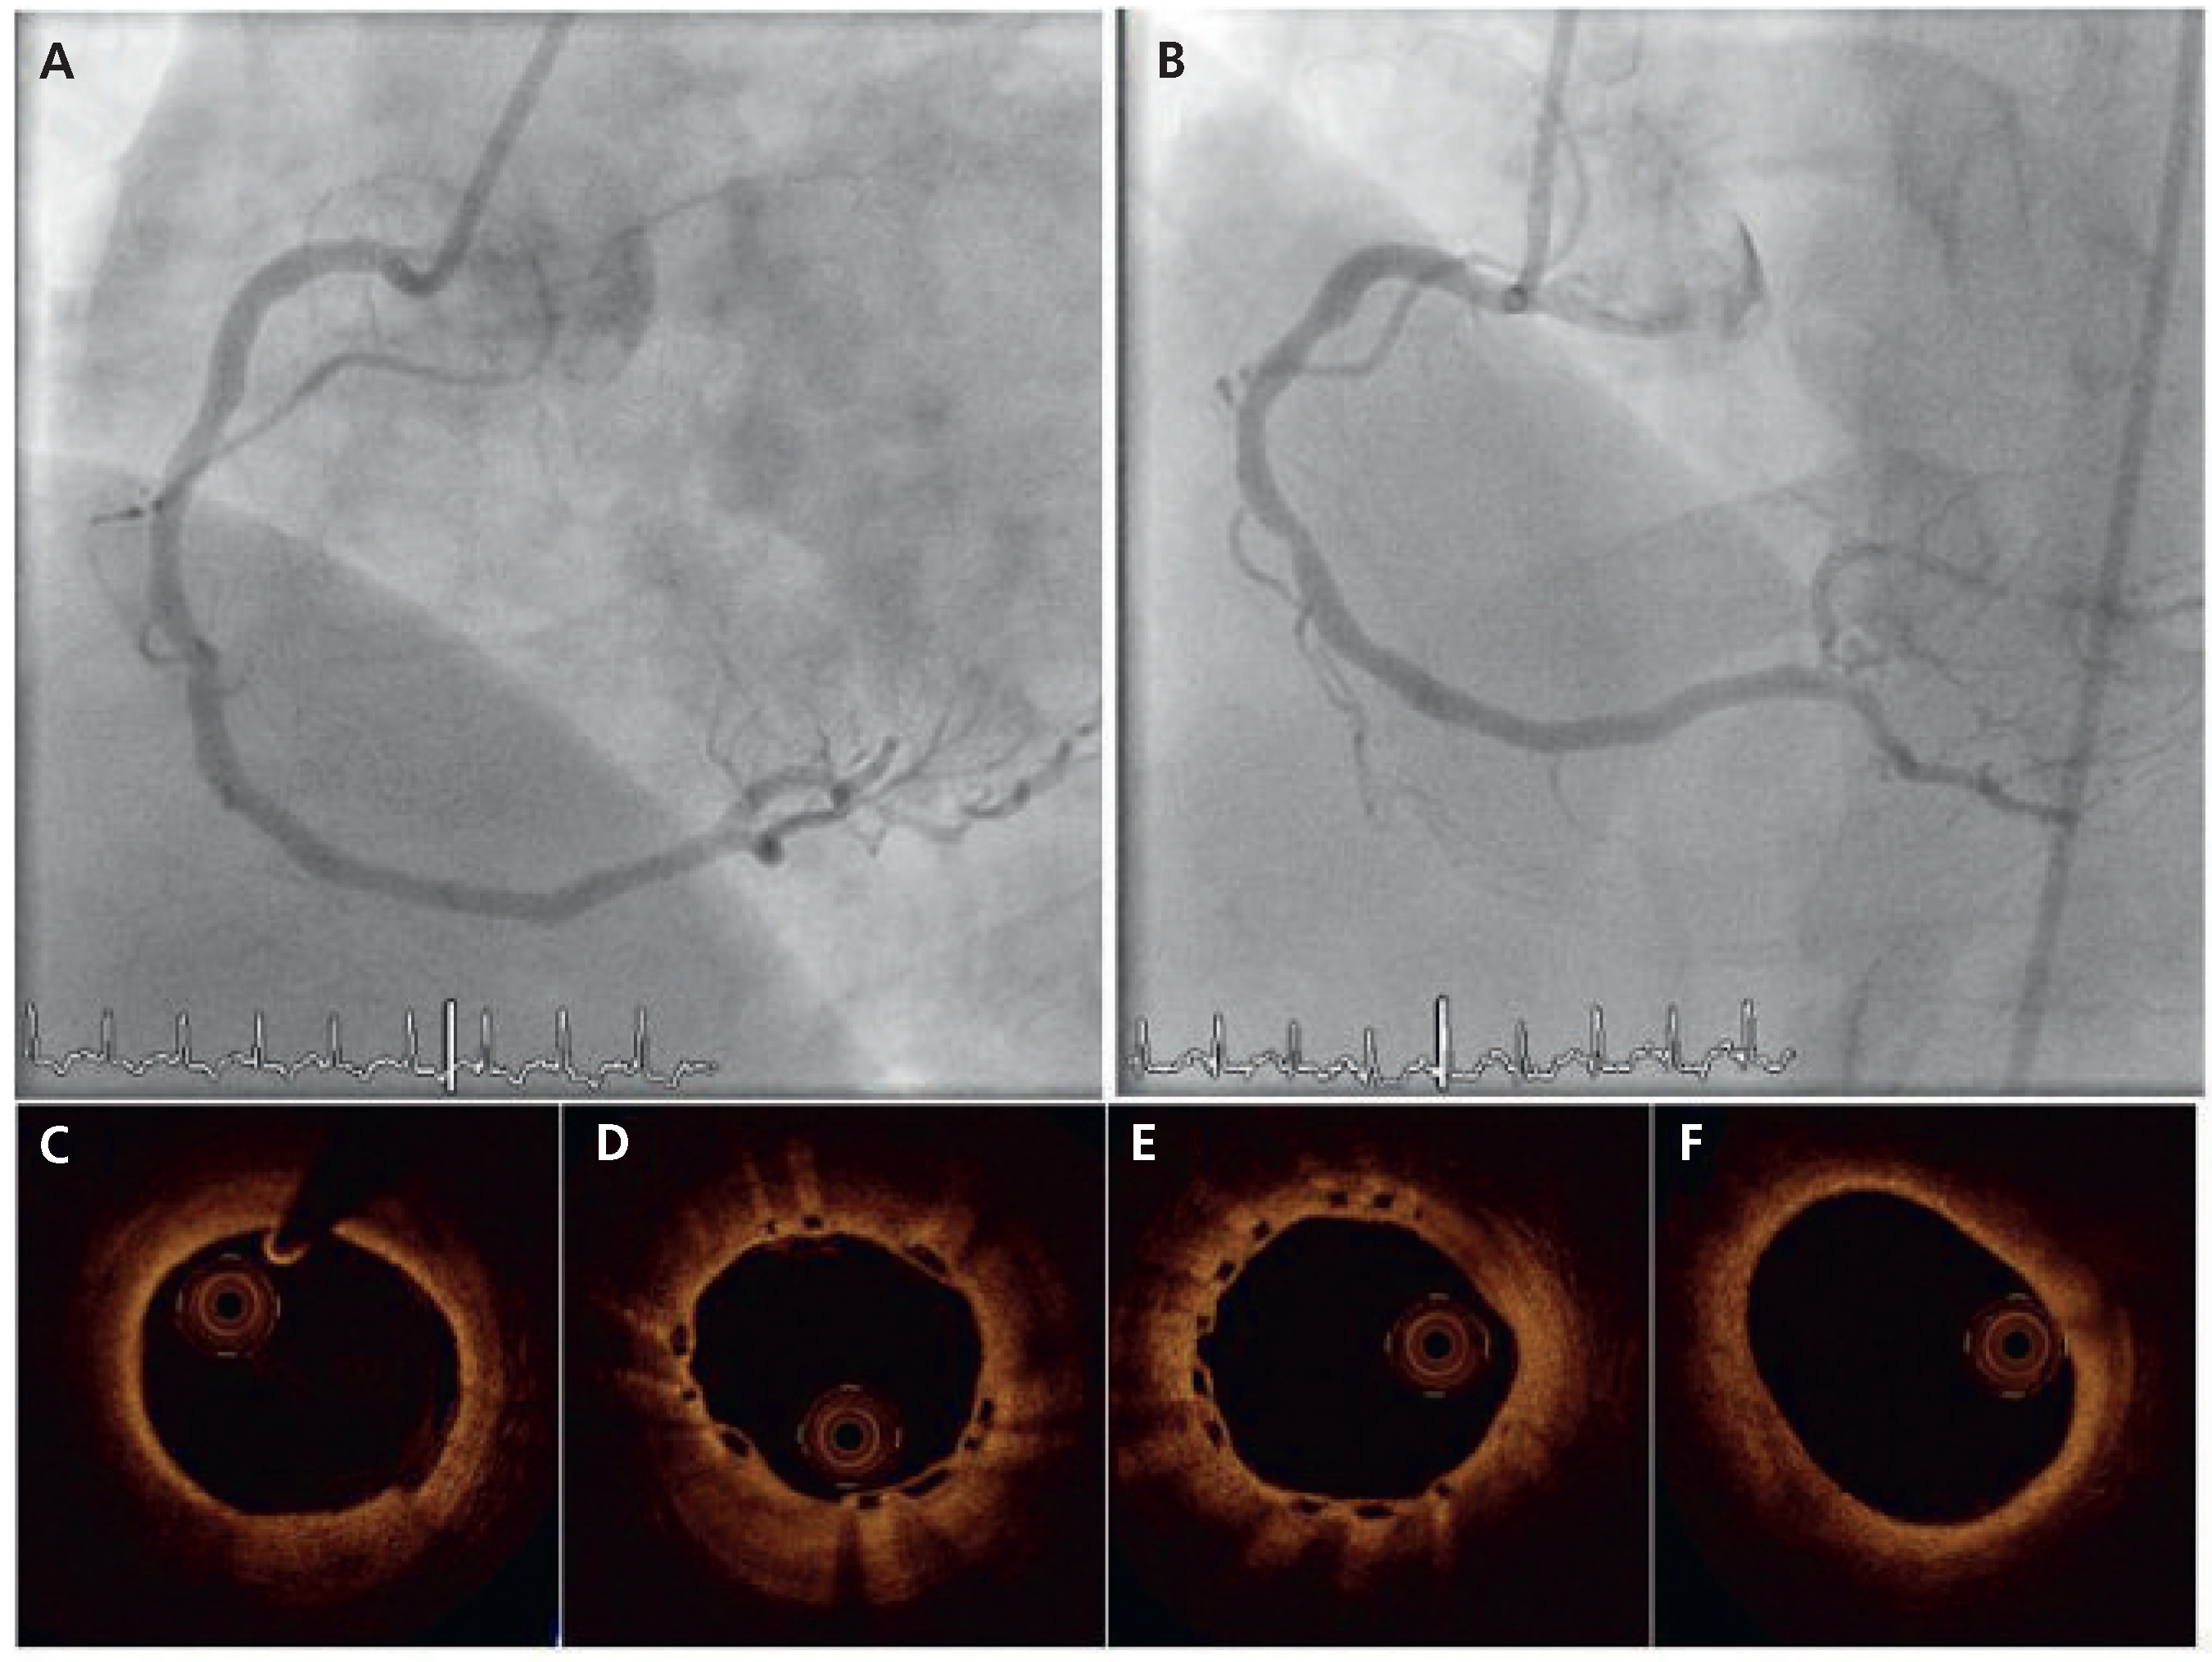

Figure 2.

Angiographic (A,B) and OCT findings (C–F) at 6-month angiographic follow-up.